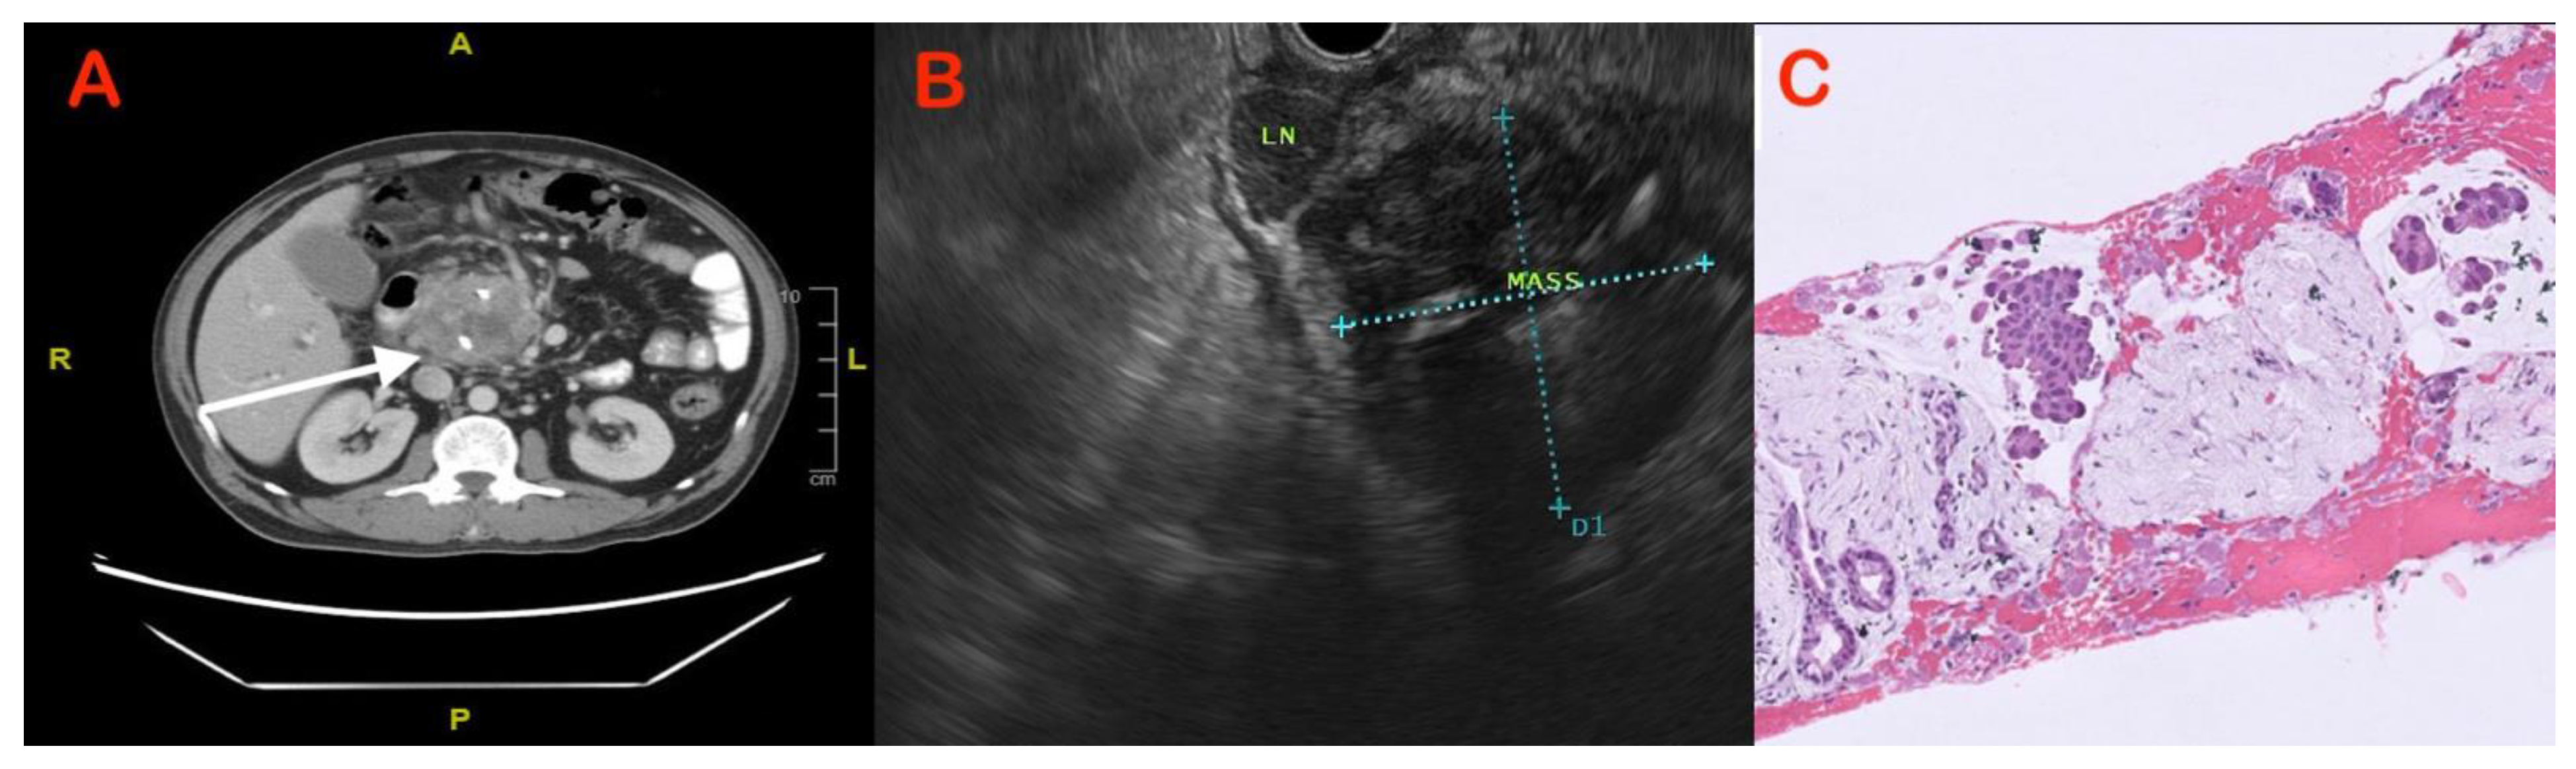

5.3. Endoscopic Modalities